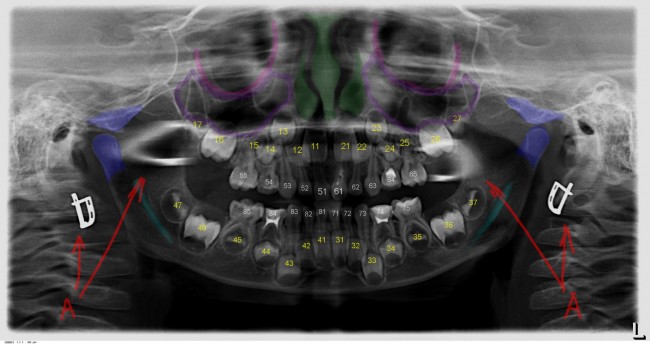

Многие об этом забывают, но в дентальной имплантации расходниками являются, в том числе, инструменты для подготовки лунки и установки имплантата. В частности, спиральные и лепестковые фрезы для препарирования костной ткани имеют ресурс 20-50 рабочих циклов, по истечении которого они выходят из строя: